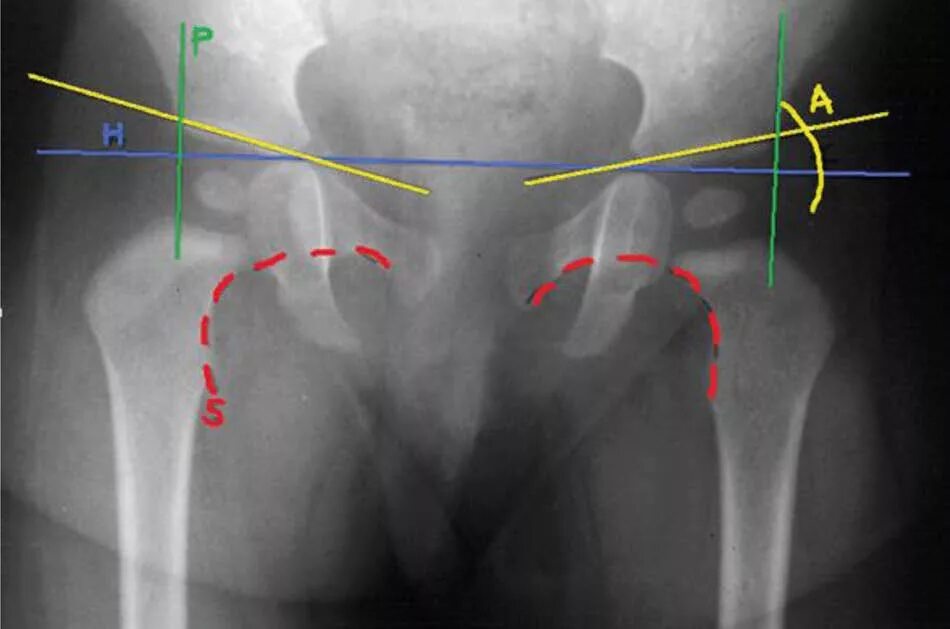

Вывих тазобедренного у взрослых